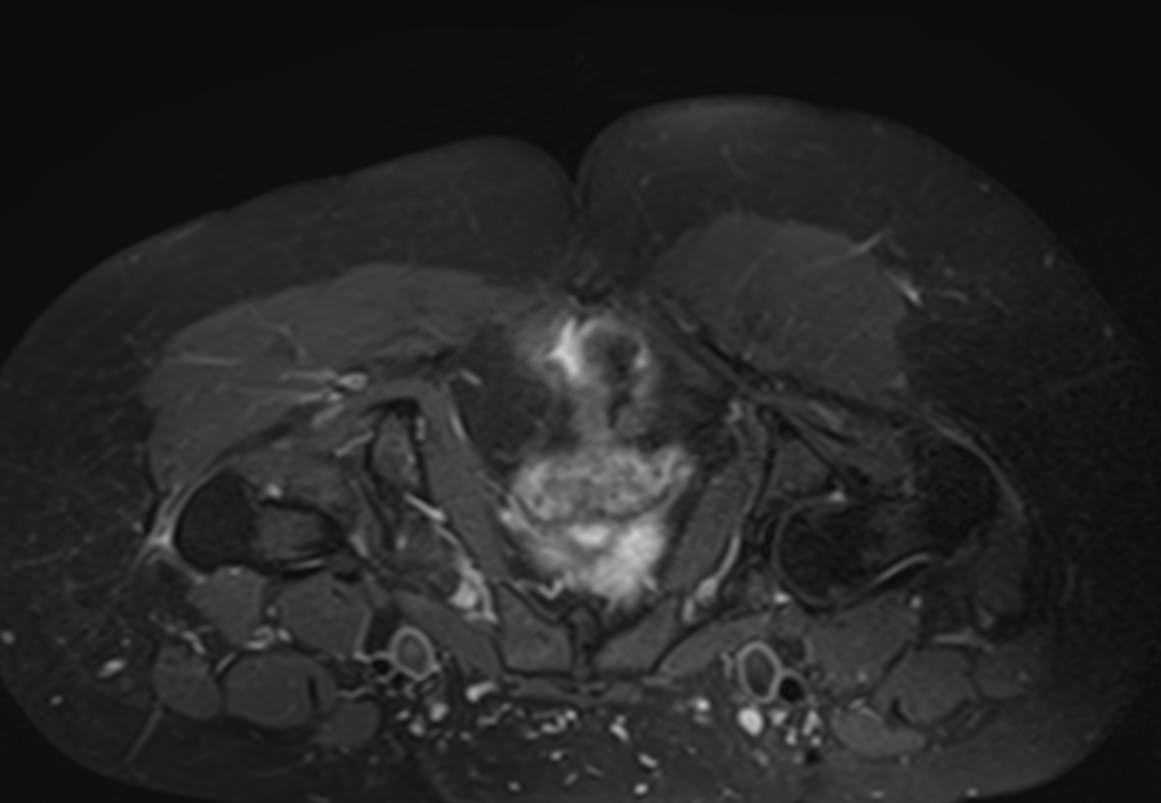

МРТ данной анатомической области выполняется в большинстве случаев в стандартном режиме без применения контрастного усиления. Однако при подозрении на развитие опухоли необходимо введение контрастного препарата. Для этого используется контрастное вещество, созданное на основе гадолиния (металл, обладающий особыми свойствами в зоне действия магнитного поля). Контраст избирательно накапливается в очагах поражения и обусловливает их яркое свечение под влиянием магнитного поля томографа. Это позволяет, в частности, выявлять опухоли на ранних стадиях развития и дает исчерпывающую информацию о структуре опухолевого образования, его границах, степени кровоснабжения и распространения на близлежащие органы и ткани.

- Доброкачественные и злокачественные опухоли, которые располагаются в мягких тканях ягодичной области.